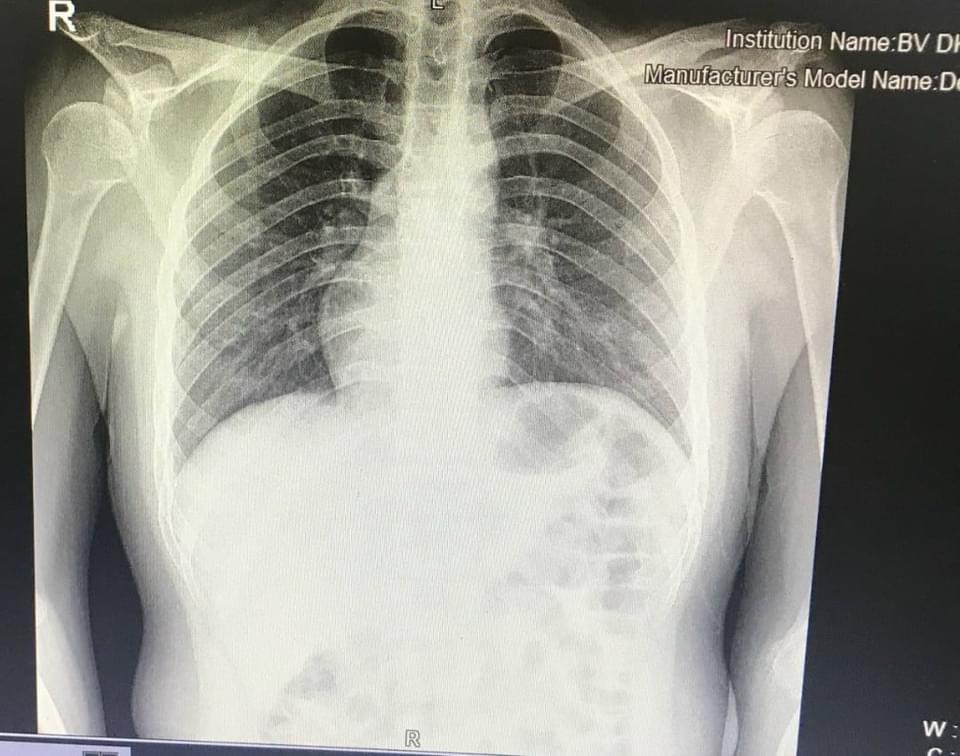

Hình ảnh chụp phim X-quang của bệnh nhân cho thấy trái tim nằm ở lồng ngực phải. (Ảnh: BVCC)

Ngay sau khi tiếp nhận thông tin, bệnh nhân H được các bác sĩ thăm khám rất cẩn thận, tỉ mỉ và làm các chỉ định cận lâm sàng cần thiết để xác định nguyên nhân gây đau như siêu âm ổ bụng, chụp X-quang, xét nghiệm máu… Khi có kết quả siêu âm, chụp X-quang, bệnh nhân được chẩn đoán Viêm ruột thừa. Và có một điều khiến các bác sĩ rất bất ngờ đó là hình ảnh trái tim trong lồng ngực bệnh nhân H ở vị trí đảo ngược so với người bình thường.